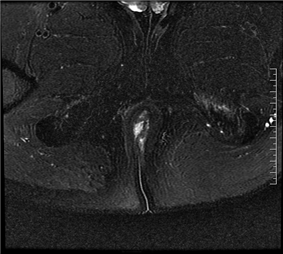

磁共振(MRI)检查的目的是为了判断内口、外口的位置、数目;瘘管走形、瘘管与括约肌复合体之间的关系;判断是否合并脓肿;寻找分支瘘管或窦道;判断活动性与非活动性,从而为临床诊断与治疗规划提供重要参考。

(MRI影像示意图,展示肛瘘常见表现)

在MRI图像中:

◆ 活动期肛瘘MR常表现为T2WI高信号,增强明显强化;

◆ 寻找内口以T1WI增强序列最佳,其次为T2WI抑脂序列,内口影像表现为括约肌内点状T2WI高信号,明显强化或括约肌受牵拉,括约肌间隙消失;

◆ 直径<1CM为瘘管,瘘道的管径最宽处直径>1CM的局限膨隆为脓肿;

◆ 肛瘘愈合期或慢性期,T2WI常表现为低信号,强化减弱或无强化。